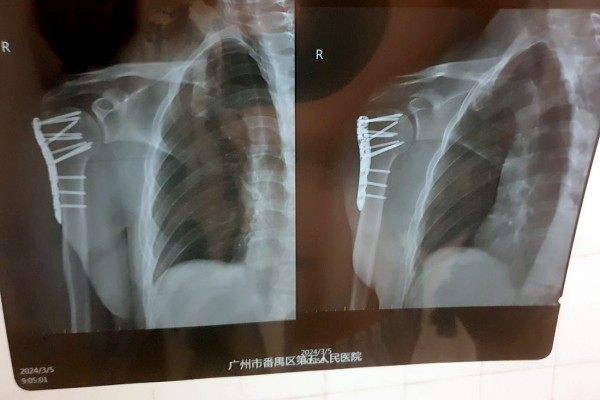

— Рука начала стремительно синеть, мне сразу сделали рентген и МРТ. Достаточно быстро стало понятно, что у меня перелом плеча со смещением. Боль была очень сильная, я не мог нормально пошевелить рукой. Врач сказал, что, возможно, потребуется операция. Мне пытались вправить плечо, но безуспешно. В итоге направили в хирургический отдел стационара, — говорит собеседник.

— В операционной мне сделали укол в шею. Затем правую руку будто ударило током пару раз, а потом я вообще перестал ее чувствовать вместе с плечом. Врач и несколько крепких китайских медбратьев после серьезных усилий наконец смогли вправить мои кости. Затем снова сделали снимок, чтобы в этом убедиться. После этого привезли в палату, и я смог немного поспать, — рассказал белорус.

Операцию все-таки пришлось сделать. По словам врачей, в противном случае кости срастались бы очень долго.

— Все это заняло около двух часов. Процесс не был приятным, так как я был в сознании и ощущал все манипуляции, проводимые на костях моего плеча, включая сверление, например. Была установлена пластина, которая зафиксировала поврежденные кости в правильном положении. После операции побочных эффектов не было, однако в течение еще шести часов врачи подключали различные датчики для контроля состояния. Все это время нельзя было есть и пить. А рука ощущалась как кусок бревна, — вспоминает читатель.

— Китайские врачи проделали по-настоящему хорошую работу. Это подтвердил знакомый белорусский хирург, взглянув на мои послеоперационные снимки. Думаю, не последнюю роль в этом сыграло и то, что я иностранец: мне показалось, что врачи особенно старались сделать все по высшему разряду. Также это хороший пример того, что надо смотреть не на вывеску больницы. Главное — это именно врачи и их отношение к своей работе, — считает молодой человек.

Белоруса выписали из больницы спустя три дня после операции. Впереди длительная реабилитация и еще одна операция — для того, чтобы изъять из плеча металлическую пластину.